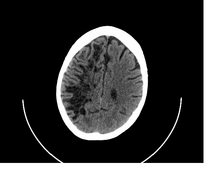

A perivascular space, also known as a Virchow–Robin space, is an immunological space between an artery and a vein (not capillaries) and the pia mater that can be expanded by leukocytes. The spaces are formed when large vessels take the pia mater with them when they dive deep into the brain. The pia mater is reflected from the surface of the brain onto the surface of blood vessels in the subarachnoid space. Perivascular cuffs are regions of leukocyte aggregation in the spaces, usually found in patients with viral encephalitis.

Perivascular spaces are extremely small and can usually only be seen on MRI images when dilated. While many normal brains will show a few dilated spaces, an increase in these has been shown to correlate with the incidence of several neurodegenerative diseases, making the spaces a popular topic of research.[1]

Perivascular spaces are distinguished on an MRI by several key features. The spaces appear as distinct round or oval entities with a signal intensity visually equivalent to that of cerebrospinal fluid in the subarachnoid space.[4][7][8] In addition, a perivascular space has no mass effect and is located along the blood vessel around which it forms.[7]